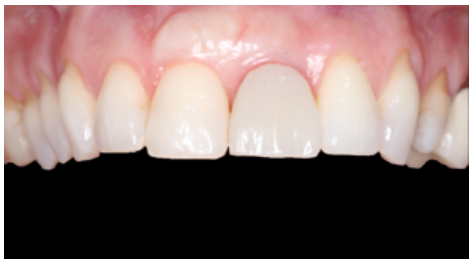

Clinical case: A 32-year-old female patient who attended for a possible root fracture of the upper left central incisor (ULCI), accompanied by a periodontal abscess at the bottom of the vestibule of the same tooth. A clinical and radiological examination established that the prognosis of the ULCI was unfavourable for conservative treatment. After evaluating the clinical features of the case, the treatment plan to extract the ULCI followed immediately by an osseointegrated implant (OII) and loading of a provisional prosthesis on the implant.

Conclusions: Rehabilitation on implants in situations of tooth loss in the aesthetic anterior sector, especially in young patients, requires a multidisciplinary treatment plan to extract the tooth and insert an OII in the correct 3-dimensional position. Various aspects need to be taken into account for this, particularly the residual remaining bone, the position of the gingival margin and preservation and conditioning of the peri-implant hard and soft tissues by means of grafts and proper handling of provisional prosthesis, until an ideal emergence profile and gingival contour is achieved before the final crown.

The benefits of immediate loading include a marked reduction in surgical interventions, less temporary dilation of the treatment and even better psychological and social wellbeing for the patient. In cases with a significant aesthetic requirement, immediate loading or provisionalisation, and post-extraction placement of the OII minimise alterations due to tooth loss and maintain the emergence profile, soft tissue contour and gingival papillae5-7.